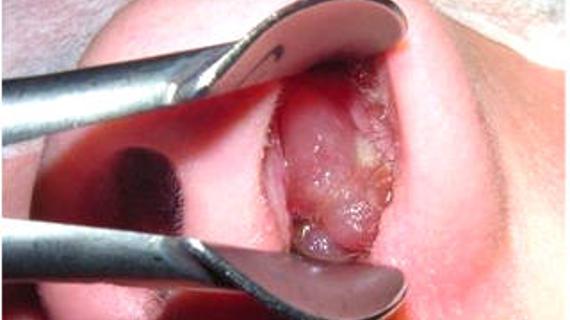

Если выдавил герпес, что делать? Такой вопрос интересует многих людей, и чтобы дать на него ответ, нужно сначала узнать, что такое герпес. Герпес - это общее определение для всего спектра...

Выясним, можно ли идти к стоматологу с герпесом на губе. Чтобы ответить на этот серьезный вопрос, давайте сначала разберемся в том, что представляет собой столь...